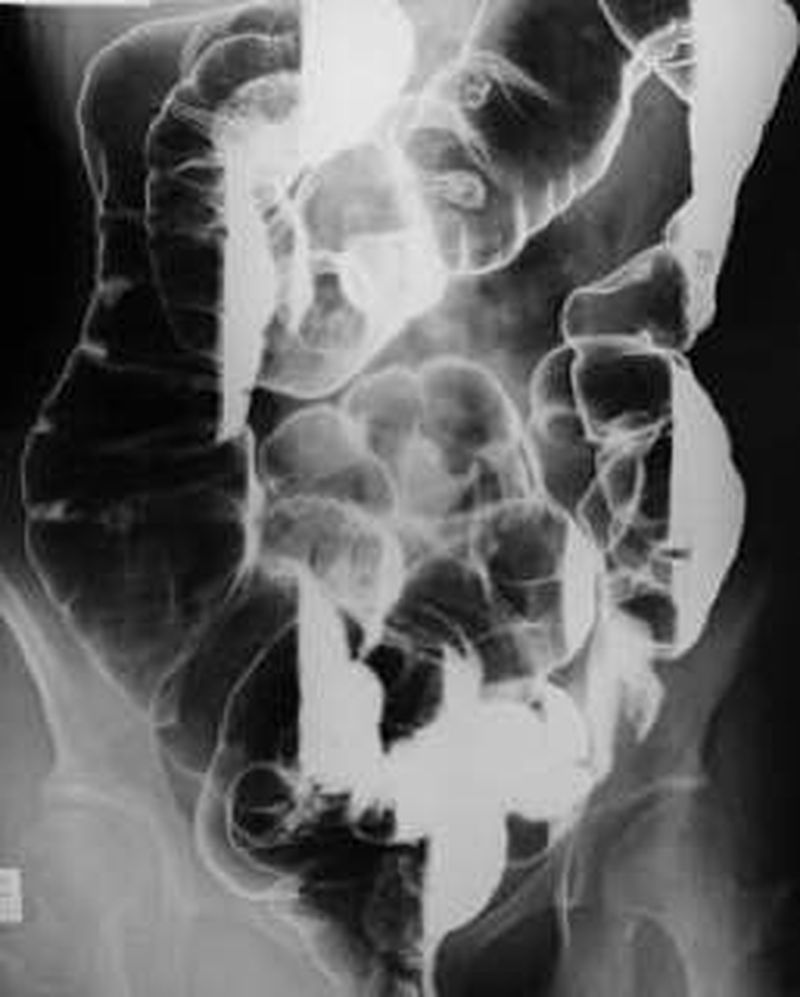

Diagnosis please

Toxic megacolon?π€